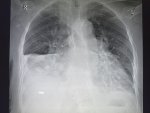

Здравствуй двачик, сегодня мы с вами опять будем играть в рентгенолога, я вам буду постировать фоточ

Здравствуй двачик, сегодня мы с вами опять будем играть в рентгенолога, я вам буду постировать фоточки, а вы узнавать пиздецомы на них.

>>327474821

Пневмония в нижнем сегменте.

Ну или тубер

Аноним 09/12/25 Втр 07:51:12 #13 №327475010

>>327475007

Там еще жижа и плеврит

Гидроторакс с линией демуазо?

Ну чот, а метастазы чому игноришь?